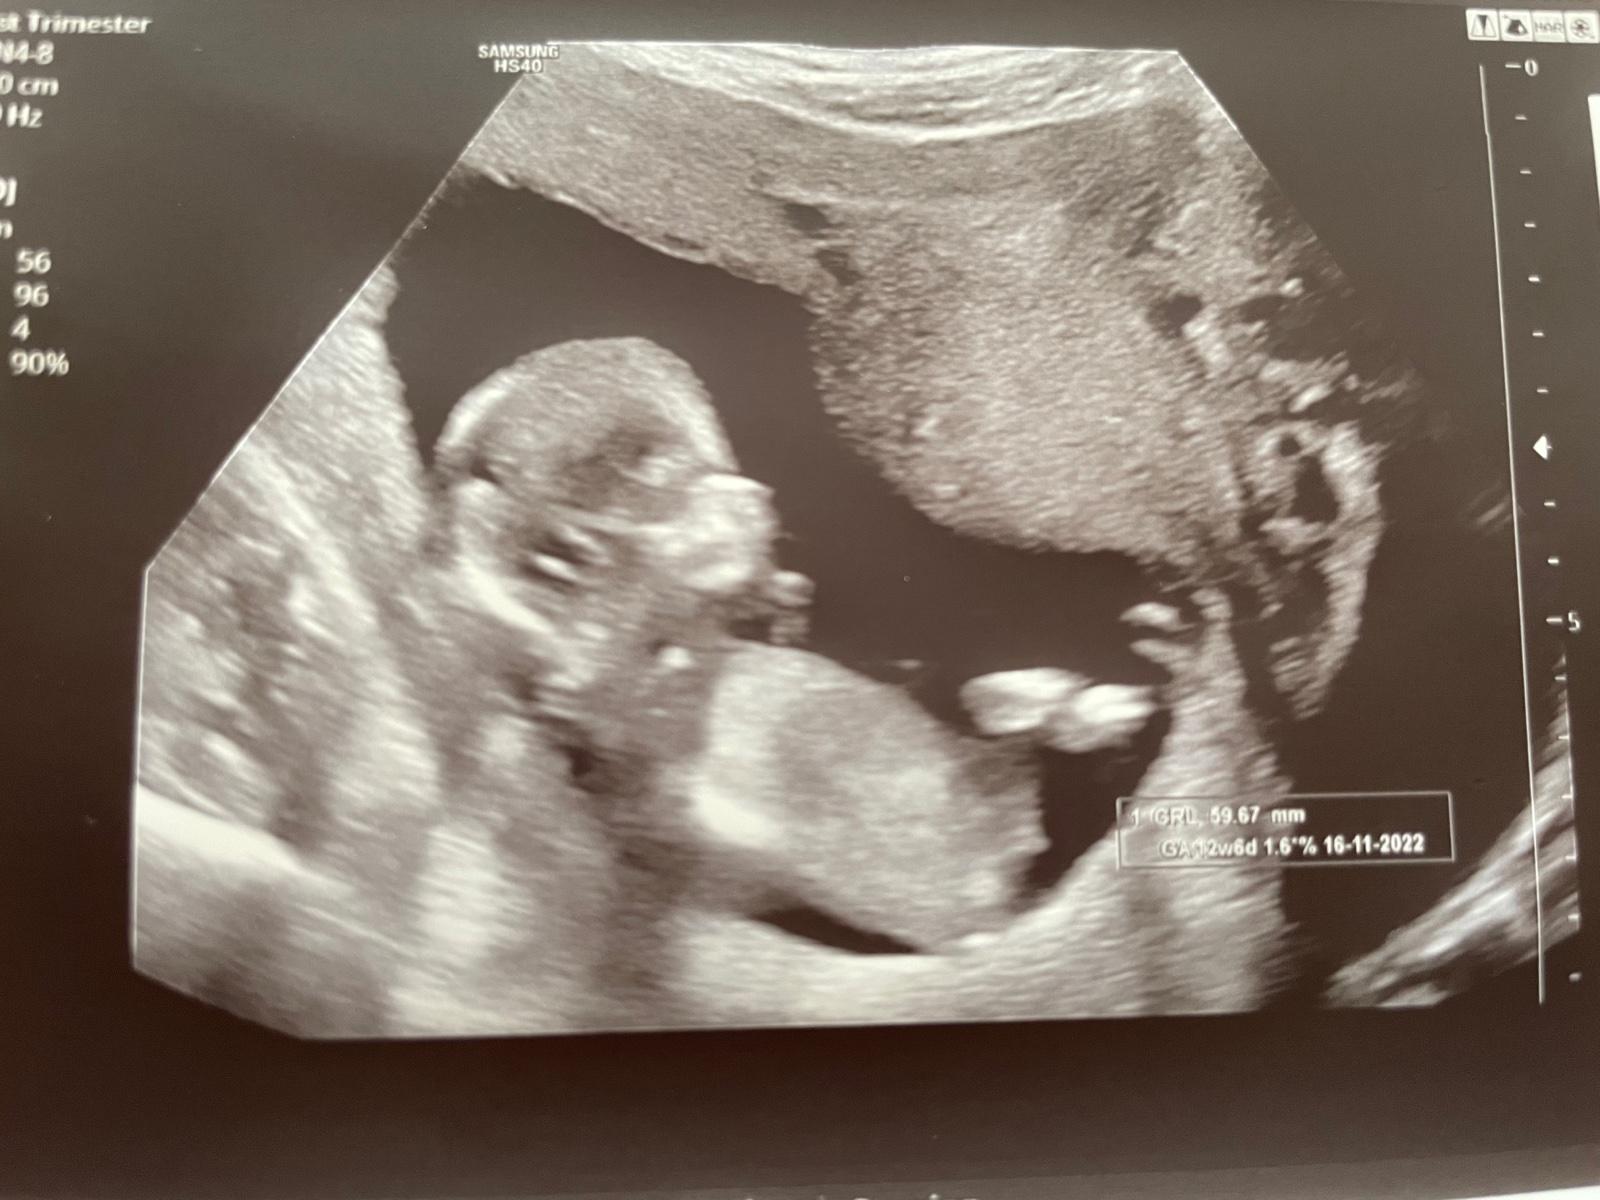

chtěla bych se zeptat, zda lze z této fotky určit pohlaví miminka. Stáří 13+5 tt.

bohužel nelze ☹